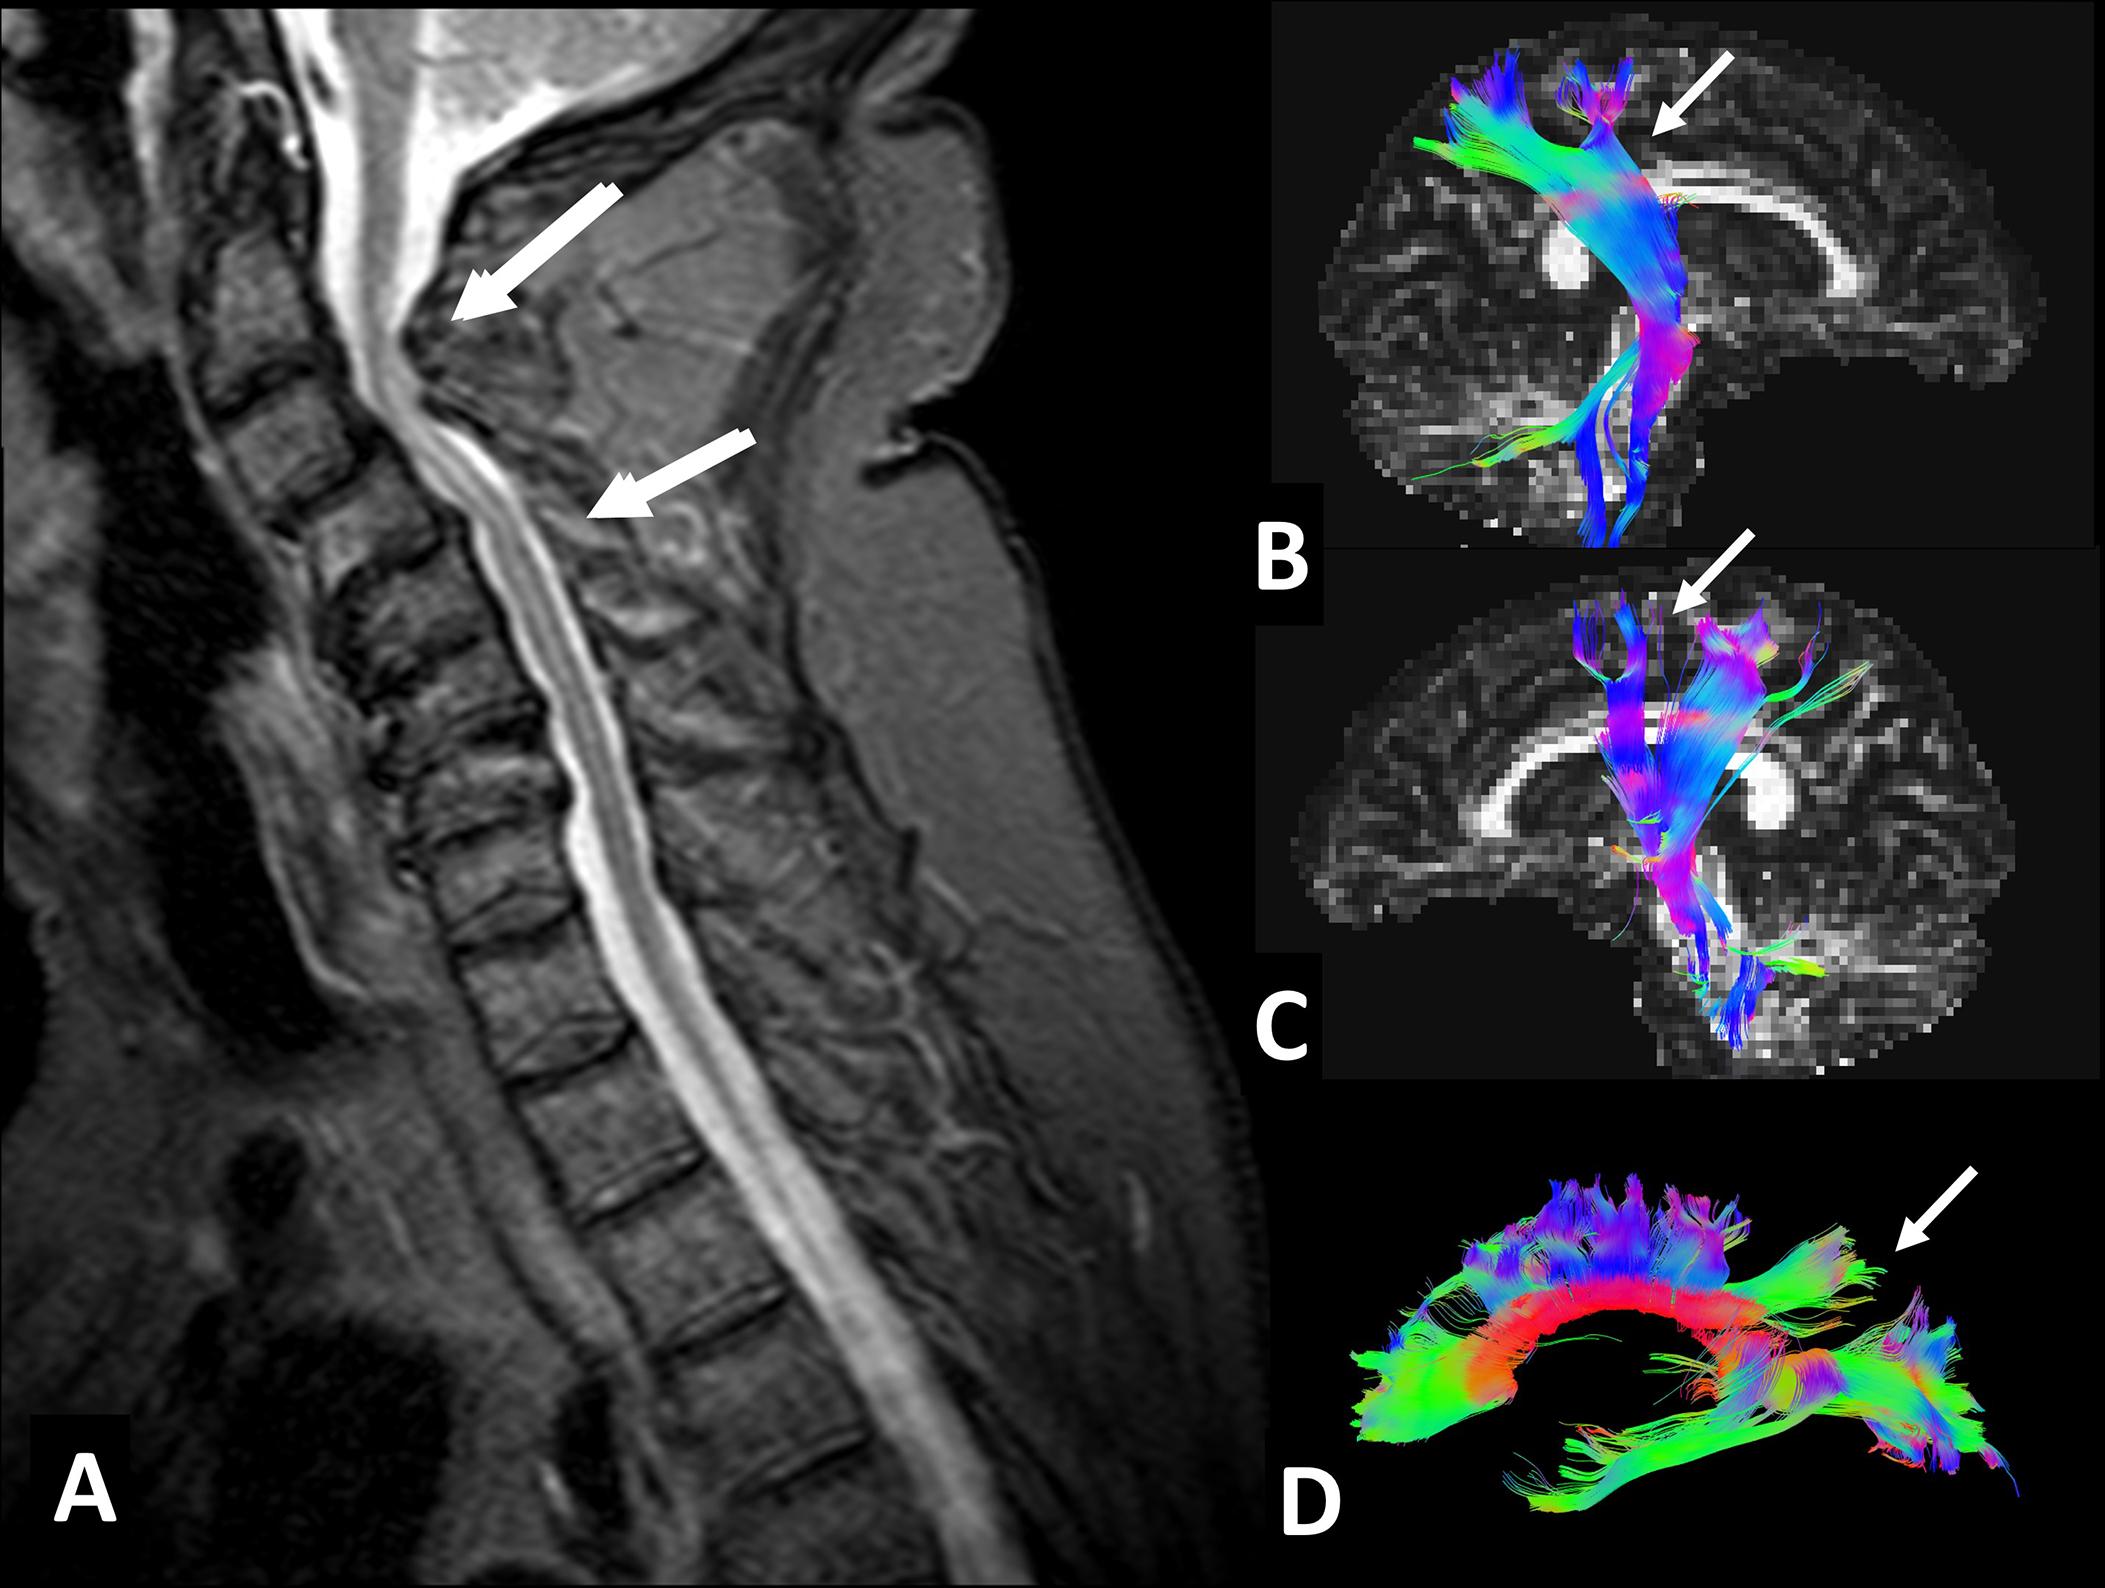

Fig. 5, Tractography results obtained in a patient with cervical spondylosis myelopathy. (A) Sagittal STIR of a 69-year-old male with cervical spondylosis and myelopathy at C2-C5 levels, significant cervical lordosis loss, and several diffuse herniated discs from C2 to C7. Clinically the patient only presented bilateral manual clumsiness. No cervicalgia or cervicobrachialgia was present. (B, C, D) Tractography results suggested significant bilateral and symmetrical axonal damage affecting both corticospinal tracts at the distal-anterior regions (B, C) and the corpus callosum (A) at the superior and posterior parietal projection fibers of both hemispheres (see arrows) . Commissural fibers were preserved.